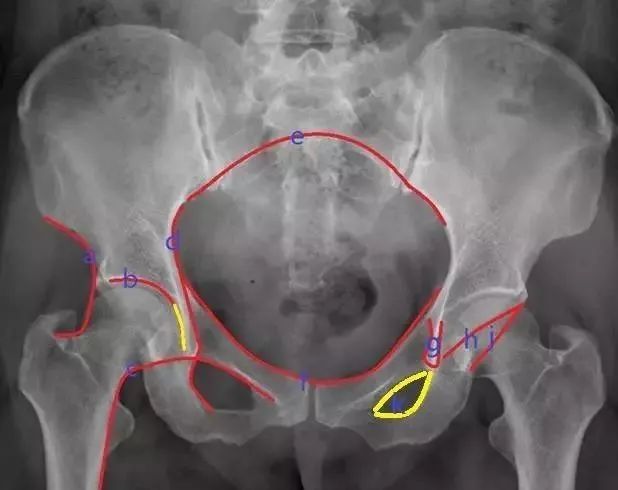

图1 骨盆正位片

(1)髋骨的X线解剖 常规投照正位(图1)。在X线像上,构成髋骨的三个部分融合于髋臼,可清晰分辨。髂骨翼的内侧1/4影像与骶骨影像重叠,外侧3/4因有髂窝而较透亮。髂嵴阴影较致密,边缘不光滑,外侧可见髂前上棘影,髂后上棘则重叠于骶骨影内。弓状线及骨盆腔内侧壁形成复合影像,外侧可见弧形的髋臼阴影。髋臼阴影的上段粗而致密,中段较细,它向下绕过髋臼切迹前部的下缘,与耻骨体的内面形成一条“U”形的致密线,称为泪滴线(Koekler泪滴),泪滴线二脚之间的距离,即髋臼窝的厚度。髋臼内下方的透亮影为闭孔。闭孔影的上界是耻骨上支、外侧界是坐骨体的下份,坐骨结节阴影与其重叠。坐骨棘的阴影呈三角形突向盆腔。

(2)骨盆的X线解剖 骨盆一般投照前后位,检查骶、尾骨时可加照侧位,检查骶髂关节时应加照45°斜位,产科骨盆测量另有其特殊投照方法。骨盆前后位片上,骶骨中线应通过耻骨联合。骶髂关节左右对称,关节间隙下半部分可以显示,上半部常投影出模糊双线影。界线的影像在女性呈卵圆形,在男性略呈鸡心形。髂嵴连线影正好通过第4、5腰椎间隙。由髂嵴影向外可追踪到骼前上、下棘,由髂前下棘到股骨颈外上缘的连线称髂颈线,用以判定髋关节是否正常。正位片上,可以测量耻骨下角,男性为锐角,女性为钝角。

女性骨盆径线的测量,可以采用正位(见图1)和侧位。正位片上,界线影像最远点连线为入口横径,正常为12.3cm;两侧坐骨棘连线为中骨盆横径,正常为10.5cm;两侧坐骨结节间距为小骨盆出口横径,正常为11.8cm。侧位片上,耻骨联合后缘上端到骶骨岬连线为小骨盆入口前后径,正常为11.6cm;耻骨联合后缘下端和坐骨棘中点的连线延长到骶骨的前缘,为中骨盆前后径,正常12.2cm;耻骨联合后下缘到骶尾关节的连线,为小骨盆出口前后径,正常11.8cm。

(3)髋关节的X线解剖 常规拍摄正位(见图1)和侧位X线片。正位线片上,因髋臼三骨之间以“Y”形软骨相连,融合之前,表现为横行带状透亮影,其宽窄随着年龄变化而改变。年龄越小此透亮带越宽;年龄越大,透亮带变窄,15~17岁左右消失。股骨头大部套在髋臼内,表面光滑,为致密的细弧线。头的中心偏后下部有一小凹陷,是股骨头凹,有时可投影到股骨头弧线内侧,显示为小环形透亮圈。侧位片上,中央的凹窝是髋臼,呈半圆形的致密线。

1、骨盆基本划线

a、Calve线(卡尔维氏线):髂骨外缘与股骨颈外缘所连成的弧线,能反应股骨头与髋臼的关系及髋臼上缘的完整性。

b、臼顶线 连接髋臼上缘的弧线,与泪滴外侧缘相续(黄线),代表髋臼的负重区。

c、shenton线(沈通氏线)耻骨下缘与股骨颈内侧缘所连成的弧线,正常时此线连续光滑,能反应股骨头与髋臼的关系。

d、髂坐线 连接髂骨内缘与坐骨内缘的曲线,正常时此线为连续光滑曲线,能反应四边体的完整性。

e、髂骶线 连接髂骨弓状线与骶骨岬的弧线,代表骨盆后环完整性。

f、髂耻线 连接双侧髂骨内缘与耻骨上缘的弧线,代表骨盆前环的完整性。

g、泪滴线(U形线)连接泪滴周围所形成的曲线,代表髋臼的内缘,一般用于髋臼假体深度的评价,髋臼内缘紧邻泪滴线的外缘。

h、前唇线 髋臼前缘所连成的弧线,代表髋臼前壁的完整性。

j、后唇线 髂骨外缘与髋臼后缘所连成的弧线,代表髋臼后壁的完整性。

K、闭孔内缘线 沿闭孔内缘所连成的弧线,正常情况下双侧闭孔对称,当骨盆旋转时可发生改变。

2、基本线标

⑴成人骨盆基本线标

a 、连接双侧髋臼顶端的连线,代表髋臼的上界及负重区。

b 、连接双侧大转子尖顶点的直线,正常通过双侧股骨头中心,一般用于股骨头置换术后股骨头高度的评价。

c 、连接双侧泪滴尖端的直线,代表双侧髋臼的最下缘,一般用于人工关节置换对髋臼假体位置的评价,正常时髋臼假体的内下缘紧贴此线的上缘。

d 、连接双侧坐骨结节下缘所成的直线,代表骨性骨盆的最下缘。

e 、连接双侧小转子下缘所成的直线,代表股骨近端最下缘。

f 、坐骨内缘与髂骨内缘的双切线,也称谓kohler线(科勒氏线),代表髋臼的内侧界,一般用于髋关节置换中假体深度的评价,髋臼陷入症或髋关节置换骨质磨锉过深时髋臼突至此线内侧。

g 、经过耻骨联合的直线,为骨盆的对称轴。

h、双侧髂骨最高点的连线,代表骨盆的最高点。

正常情况下,骨盆的六条水平线相互平行,且与经耻骨联合线垂直,当六条水平线出现不平行情况时,表示存在骨折错位或骨盆与髋臼的发育不良。